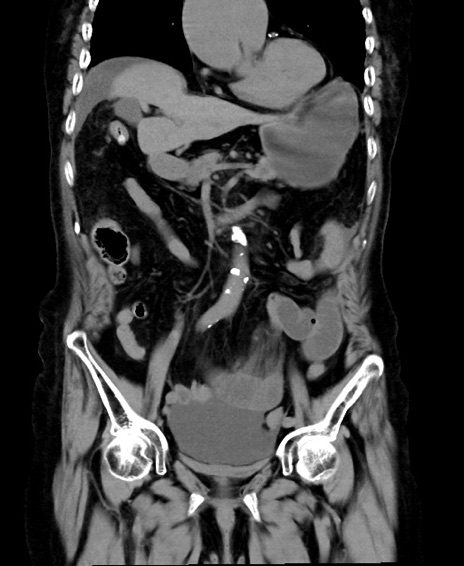

冠状断像